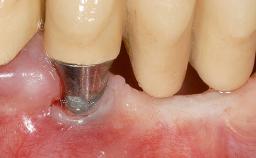

Early Implant Placement, Contour Augmentation, and Autologous Connective-Tissue Graft Using a Tunneling Technique to Replace an Upper Incisor with Generalized Gingival Recession

| # of Implants | 1 |

| Type of Implants | Reduced-Diameter|Two-Piece |

| Attachment | Reduced-Diameter|Two-Piece |

| Soft Tissue Grafting | Simultaneous |